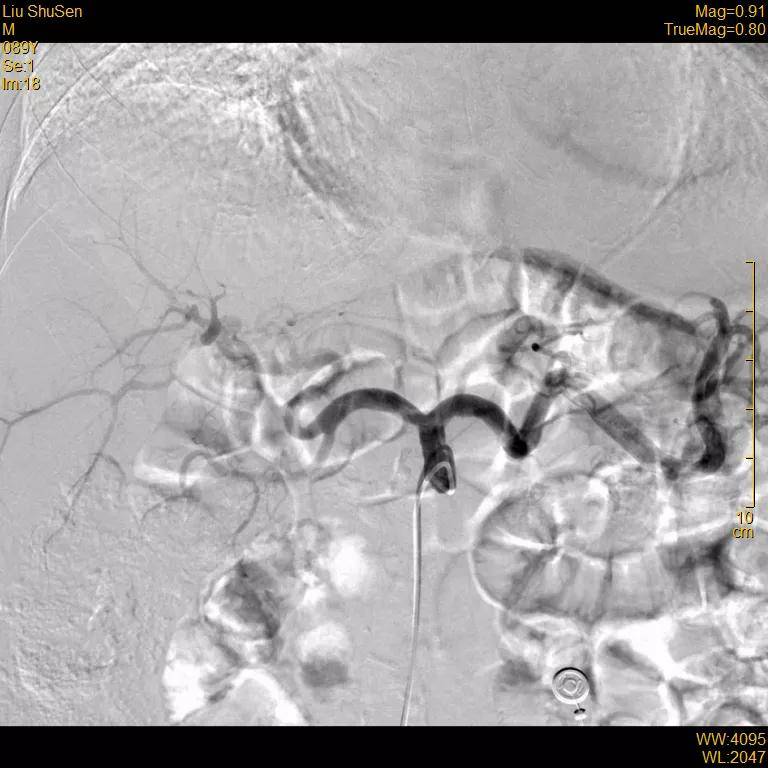

超选至肝右动脉分支2造影+栓塞

栓塞材料:表柔比星60mg+载药

微球、碘油;明胶海绵

文章图片

复查造影:原肿瘤染色不复显影

治疗后第2天 , 89岁的刘老伯就可以下床活动 。 术后3个月复查肿瘤标志物AFP明显下降 , 目前已正常 。 仅行介入治疗1次即达到CR(完全缓解 ) 。